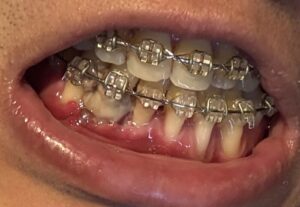

左(上)から:術後5時間後、術後17時間後、術後1週間後、術後3週間後

歯並びの変化(写真あり)

閲覧注意!

歯並びの変化を写真で載せていきます。